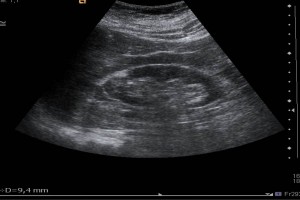

Diplomados en Ultrasonografía